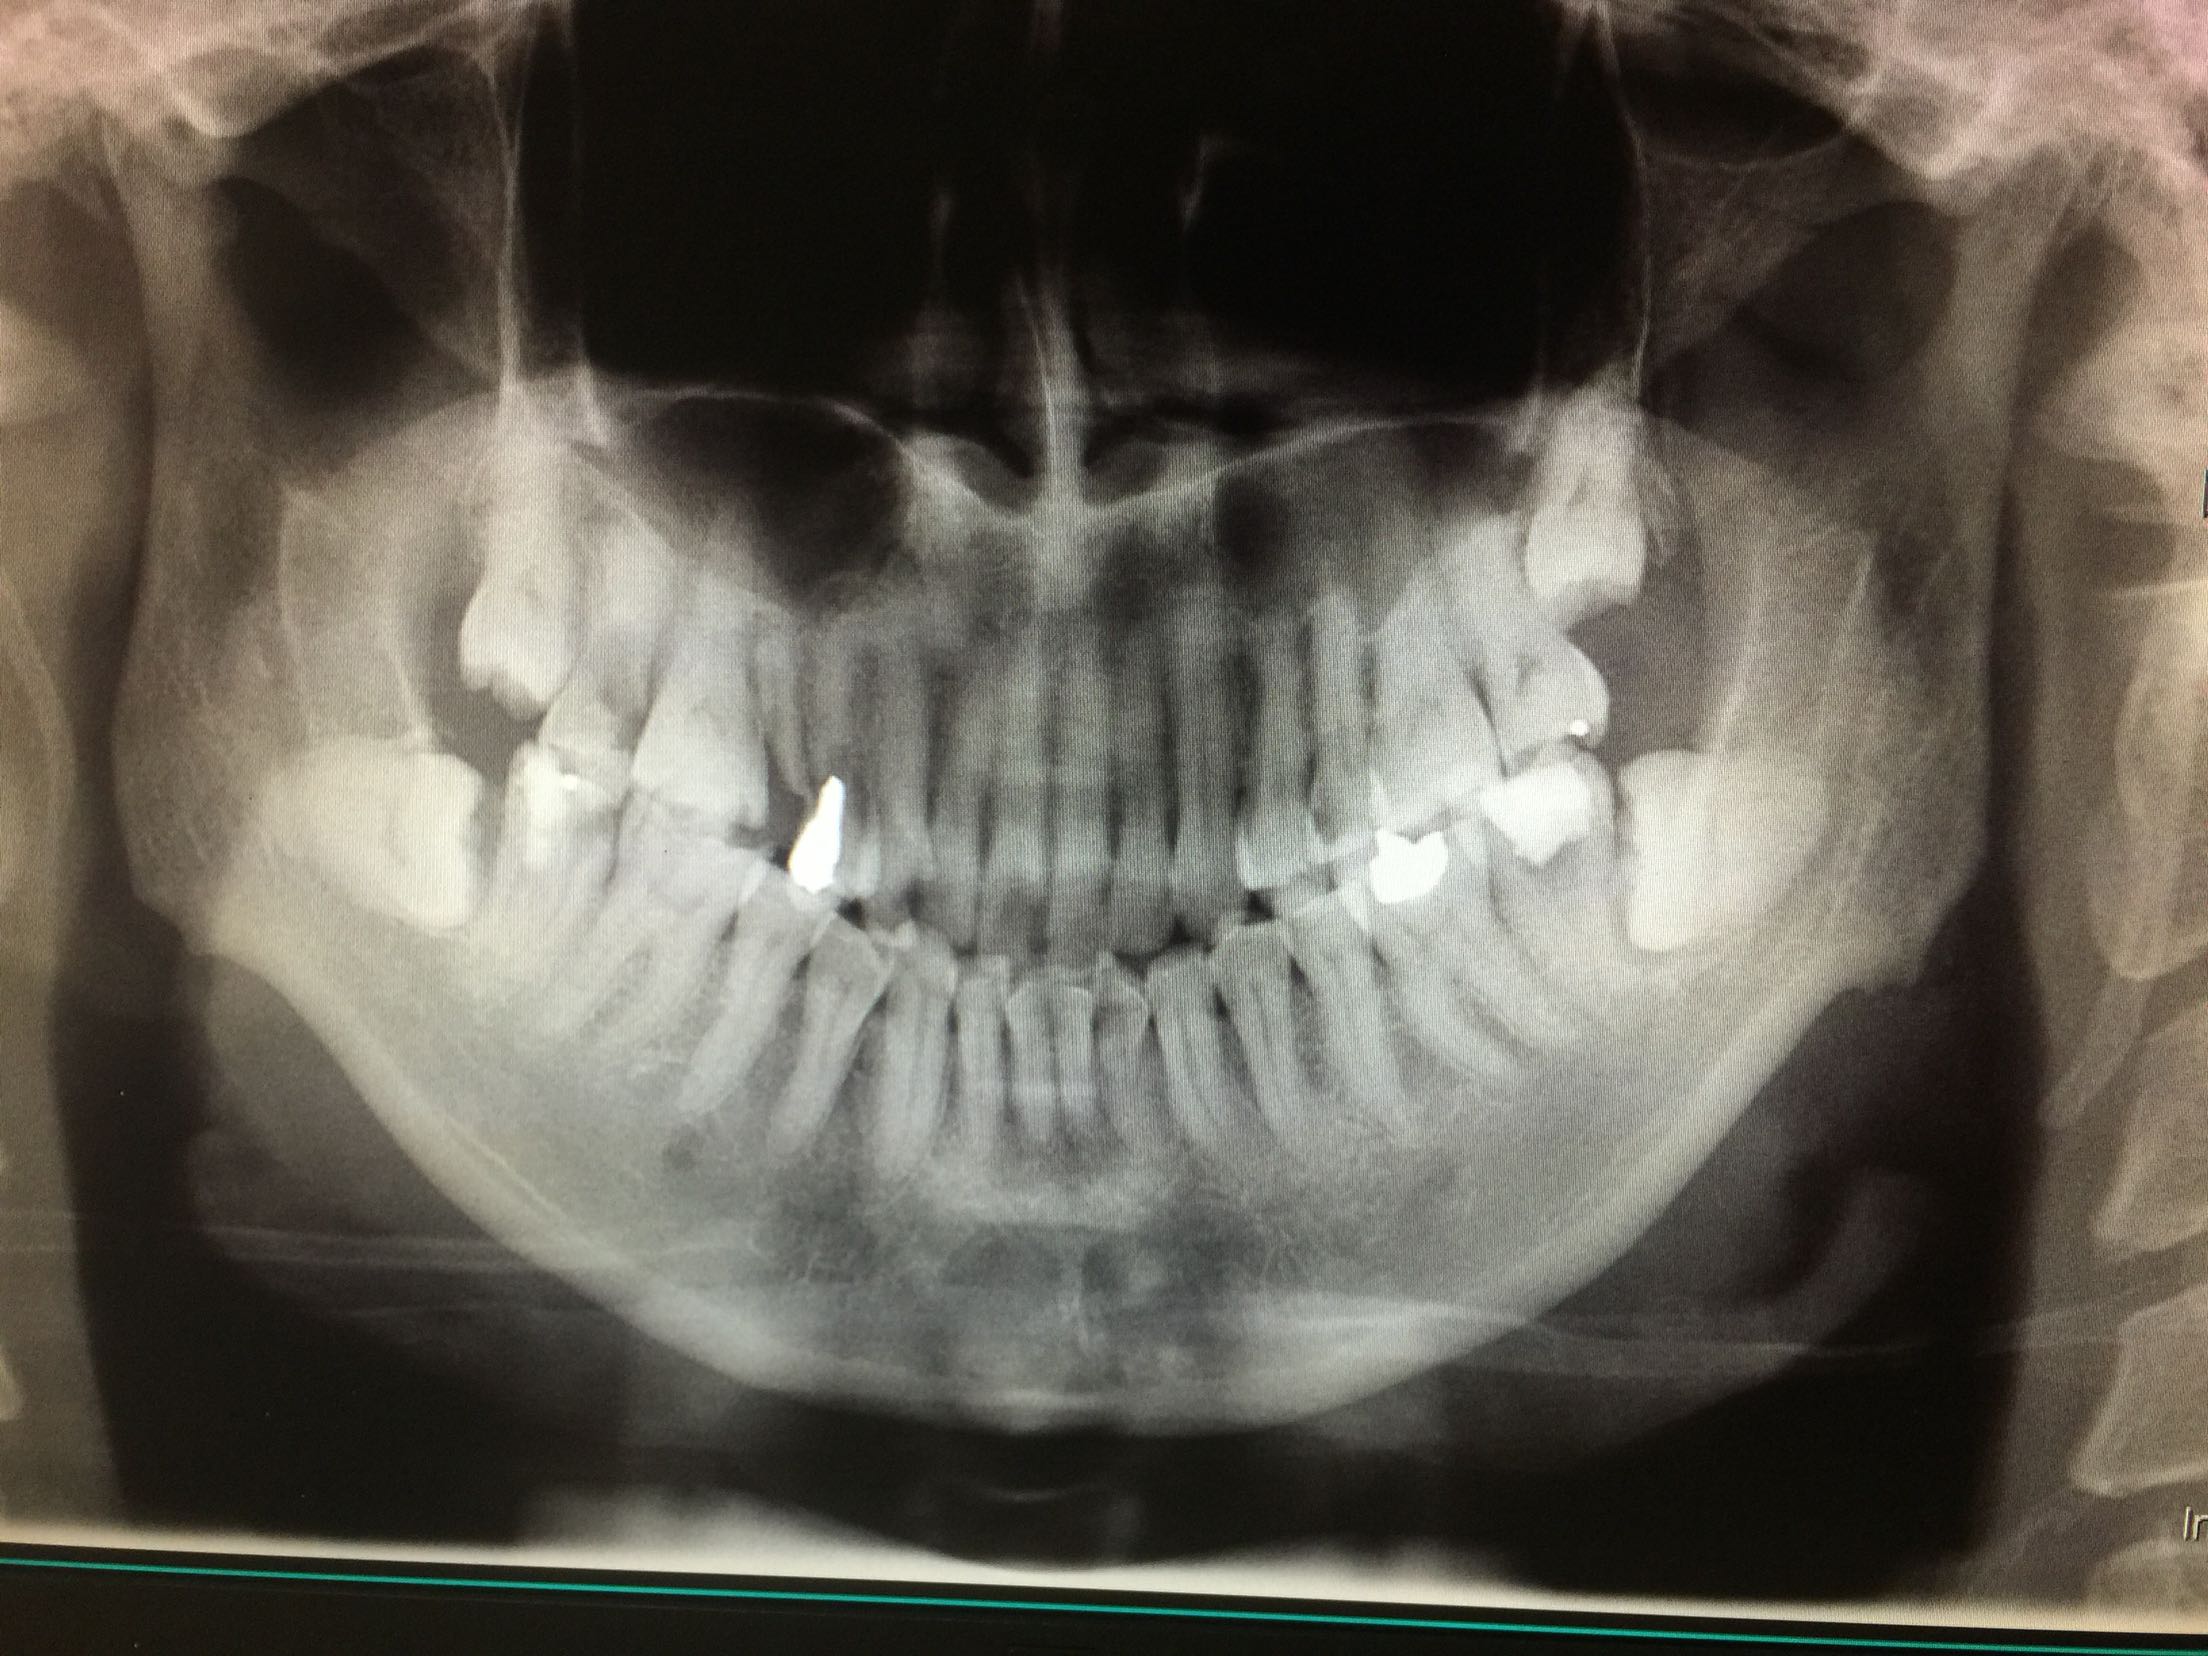

检查:37牙合面可见树脂补料,有继发龋,边缘不密合。冷+,探+-,叩-,不松。18.28.38.48近中阻生,无龋坏。 X线示:37牙合面可见高密度影像,深及髓腔,很尖区未见暗影。18.28.38.48牙近中阻生。

诊断:37牙牙髓炎 18.28.38.48牙阻生齿 治疗计划:18.28.38.48牙拔除 37牙去净原补料及龋坏后视情况制定下一 步治疗计划。 治疗:37牙去净原补料及龋坏后髓室底完整,经患者知情同意,37牙行根管治疗,探查根管口,双根管,冲洗,拍片测长,37牙远中根很尖1/3较弯曲,根管预备时要注意预弯,消毒,根管预备,根管内封进口氢氧化钙,暂封,约复诊。